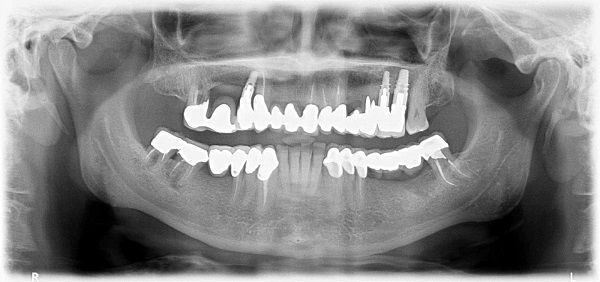

Un’ortopanoramica è un esame accurato che viene effettuato al fine di stabilire lo stato di salute dell’intero apparato dentale. Attraverso questa tecnica radiografica è possibile avere una visione d’insieme di tutto il complesso del cavo orale che include le arcate dei denti (inferiore e superiore) le ossa mandibolari e mascellari, dei seni mascellari e di ogni singolo dente.

Prima di stabilire il tipo di trattamento da applicare per una specifica patologia è essenziale prendere visione dello stato effettivo dei denti e per questo l’odontoiatra prescrive un’ortopanoramica.

I problemi dentali possono essere di diversa natura, cominciando da una carie per finire a un problema gengivale (paradontite). Altre volte la patologia può essere più complessa come danni ai tessuti interni del dente (lesioni endodontiche, tipo granulomi apicali), o persino lesioni alle ossa mascellari. In tutti questi casi siamo in grado di fare una diagnosi grazie a una serie di esami approfonditi come l’ortopanoramica ai denti che ci darà un quadro chiaro e completo della situazione.